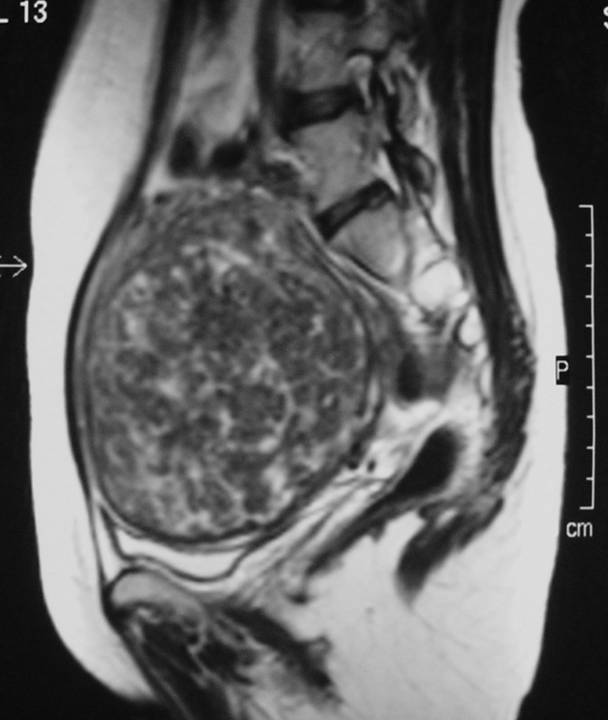

MRI pelvis of a large posterior wall fibroid with cystic degeneration …

MR imaging of atypical fibroids

Pelvic MRI for Fibroids – Why You Need an MRI to Detect Fibroids

Huge intramural fibroid | Image | Radiopaedia.org

Huge intramural fibroid | Image | Radiopaedia.org

Fibroids UFE | Body MRI

Uterine Fibroid, Mri Scan Photograph by Du Cane Medical Imaging Ltd

Fibroid | Image | Radiopaedia.org